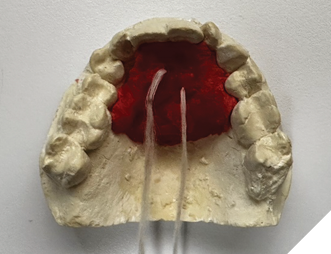

Next, a palatal jig is fabricated using fast-setting acrylic resin (Duralay) on the maxillary cast. It engages the palatal and lingual surfaces of the maxillary incisors and cuspids and is secured with dental floss embedded in the resin to prevent swallowing (Fig. 2).

Fig. 2

Once inserted and adjusted to establish simultaneous occlusal contacts in conjunction with the Gelb appliance, the palatal jig acts as a vertical stop for mandibular closure at the treatment VDO. With incisal edges and occlusal surfaces exposed, reliable occlusal registration becomes possible.